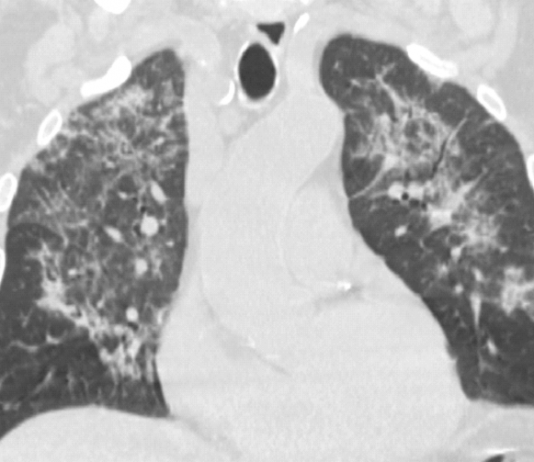

Maschio, 71 anni, diabetico noto in...